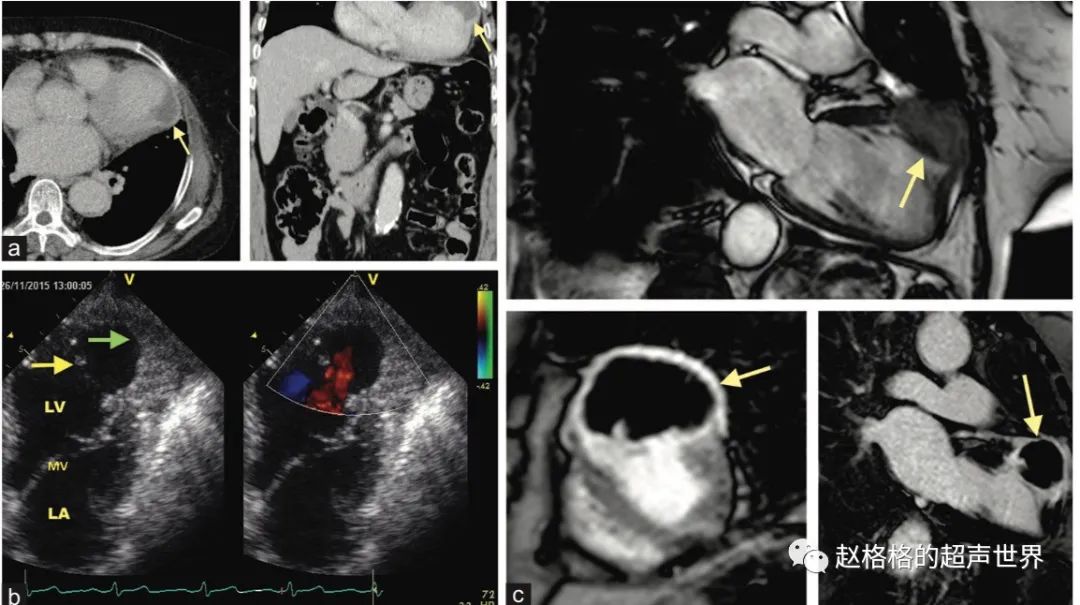

图A:左室游离壁破裂;图B:室间隔穿孔;图C:乳头肌断裂

三、乳头肌功能不全,严重时乳头肌断裂

心肌缺血如果累及乳头肌就可能导致乳头肌功能不全,严重者可能导致乳头肌断裂。

乳头肌由于缺血、坏死、纤维化或心脏重构,导致收缩功能障碍或乳头肌方位改变,导致二尖瓣脱垂;同样原因,也可引起乳头肌断裂。可导致急性重度二尖瓣反流和急性肺水肿。

四、室间隔穿孔

心梗后室间隔穿孔(VSR)是AMI后室间隔出现破裂引起的继发性室间隔缺损,可导致左向右分流、肺循环不稳定及双心室衰竭。

六、假性室壁瘤

由于心室壁破裂,破口周围由血栓堵塞或粘连,室壁瘤壁由心包膜组成。

和真性室壁瘤鉴别:假性室壁瘤的瘤颈相对较小。

和心肌夹层鉴别:通过心外膜的完整来鉴别。

七、游离壁破裂(FWR)导致心包填塞